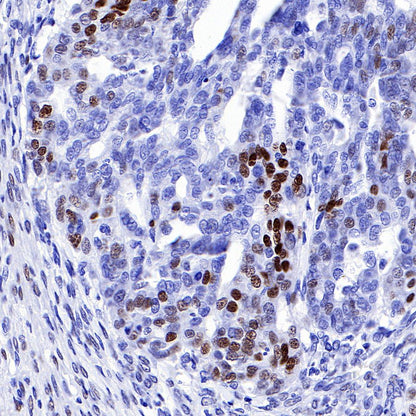

IHC shows positive staining in paraffin-embedded human breast cancer. Anti-Progesterone Receptor antibody was used at 1/500 dilution, followed by a HRP Polymer for Mouse & Rabbit IgG (ready to use). Counterstained with hematoxylin. Heat mediated antigen retrieval with Tris/EDTA buffer pH9.0 was performed before commencing with IHC staining protocol.

Negative control: IHC shows negative staining in paraffin-embedded human tonsil. Anti-Progesterone Receptor antibody was used at 1/500 dilution, followed by a HRP Polymer for Mouse & Rabbit IgG (ready to use). Counterstained with hematoxylin. Heat mediated antigen retrieval with Tris/EDTA buffer pH9.0 was performed before commencing with IHC staining protocol.